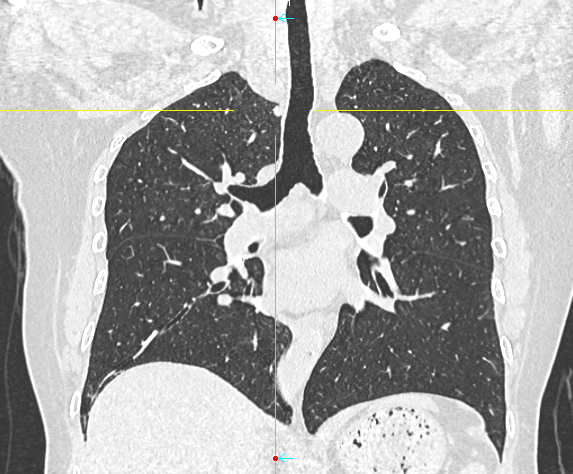

数月前,66岁的龚女士在肺癌术后随访复查中,胸部CT报告显示其右上肺新发实性结节一枚,并由刚开始发现时的5mm逐步增大至10mm。更棘手的是,这个结节位于右肺上叶尖段的纵隔胸膜下,位置极其刁钻。面对这份报告,患者龚女士陷入了深深的焦虑。因为其7年前因右中肺肿瘤行右中肺癌根治术,对于新发的实性结节为何种性质,是新发肺恶性肿瘤或是良性病变,亦或是原肺癌复发转移,目前均不能明确。辗转多家医院,得到的建议多为定期观察,等待变化或考虑创伤较大的传统穿刺活检,但结节位置非常深,单纯CT引导下定位穿刺很难精准到达,且需穿行的肺组织较多,创伤较大。

胸外科马海涛主任团队对龚女士的病情进行了深入细致的评估:结节虽小,但形态学特征具有风险,且结节逐步增大,结合既往肺癌病史,考虑肿瘤复发可能,“定期观察”方案会让患者持续承受心理煎熬。然而,传统的CT引导下经皮肺穿刺定位,对于如此深部、微小的结节,极易导致气胸、出血等并发症,风险极高。